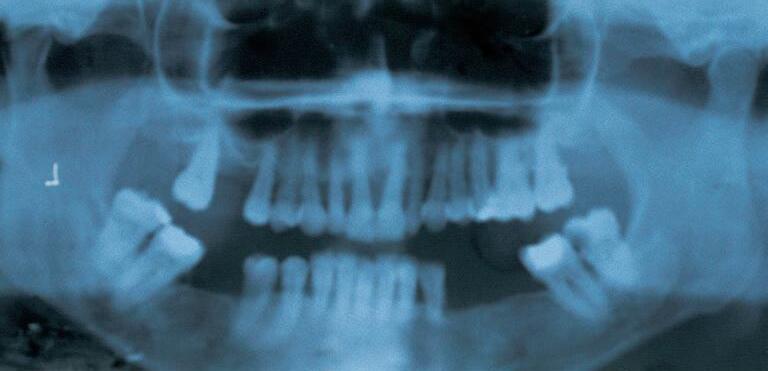

Obr.6 PanoramatickýRTGsnímek–topografickychrupsmezeramido4zubù

VoldøichovaklasifikacejetopografickáastejnìjakoklasifikacepodleEichnera aKennedyhonezohledòujevýchozípatologickýstavchrupu.Proprotetickourekonstrukcimázásadnívýznamodhadprognózyjednotlivýchpilíøùaprogreseonemocnìní,kterápacientovizpùsobiladefekt,ježjepotøebarehabilitovat.Obrázek6dokumentujetopografickýdefektchrupu,kterýbychomklinickymohlizaøaditmezi „chrupsmezeramidoètyøzubùohranièenýpilíøiI.tøídy“.Pøibližšíanalýzelzepozorovatresorpcikostipøesahující2/3koøenù.Progredujícíonemocnìníparodontu, poškodilonejenchruppacienta,aleivýškuahomogenitukostidotémíry,žeaniokamžitáextrakcevšechzubùbybezaugmentacekostinedovolilazavéstimplantáty. Retencebudoucísnímatelnénáhradybudeproblematická.

1.5RTGvyšetøení

RTGstatusapanoramatickýsnímek(OPG)dokreslujeobrazdutinyústní.Informuje okvalitìjednotlivýchzubù–pøítomnostkazu,kvalitavýplní,stavnebopotøebaendodontickéhoošetøení,kvalitaprotetickésanaceastavzávìsnéhoaparátuzubu. Zrentgenologickéhovyšetøenílzeodeèíststavalveolárníkosti,resorpcialveolu,tvar

arozsahèelistníanosnídutiny,prùbìhmandibulárníhokanáluavýstupforamenmentale.RTGinformujeopatologickýchstavech,kterénejsouklinickyzjistitelné(cysty,retinovanézuby,nádory atd.).

DalšímožnostíjevyužitípoèítaèovìzpracovanýchRTGobrazù–radioviziografie.Tamùžepomocíhistogramuposouditstupeòosteointegrace implantátù,pórozitukosti. Speciálnísoftwaremìøí kalibrovanévzdálenosti,poèítaèovýprogrammùže provéstitøírozmìrnousimulacizubuèiskupinypilíøù,lzepracovatispseudobarvami(obr.7).

Obr.7 RTG–RVG

RTGanalýzamázásadnívýznampøirozhodování,zdaindikovatfixní,nebosnímatelnounáhradu.Prospeciálníúèelysevyužívá iCTvyšetøení(tomografickýprùøez)hornínebodolníèelisti(implantáty,tumory).